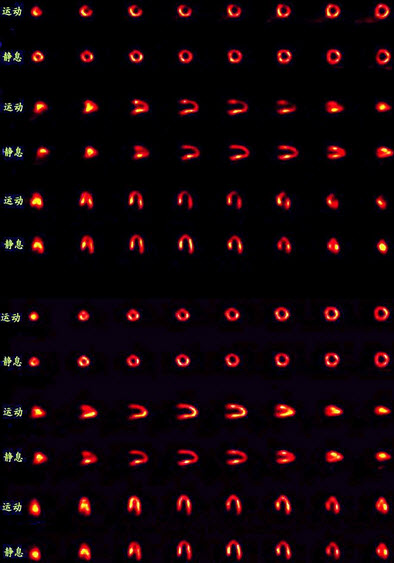

59、多项选择题

一患者的心肌灌注显像对比如图,正确的诊断是()

A.左心室前壁可逆性缺血

B.PTCA疗效显著

C.PTCA无明显疗效

D.术后再狭窄

E.以上都不是